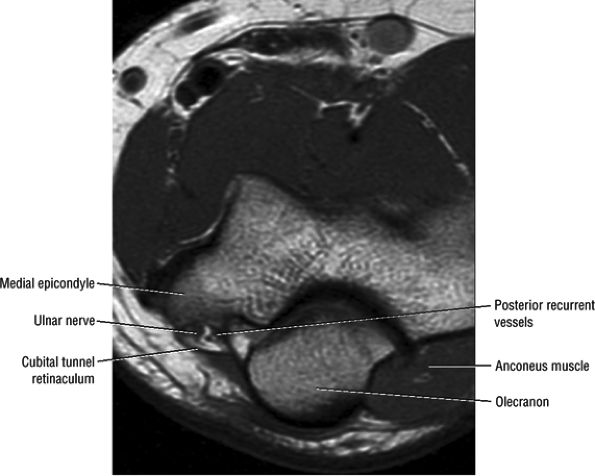

FIGURE 12.13 ● Normal MR anatomy of the ulnar nerve. Axial PD-weighted image demonstrates the ulnar nerve posterior to the medial epicondyle and medial to the posterior recurrent vessels.

|